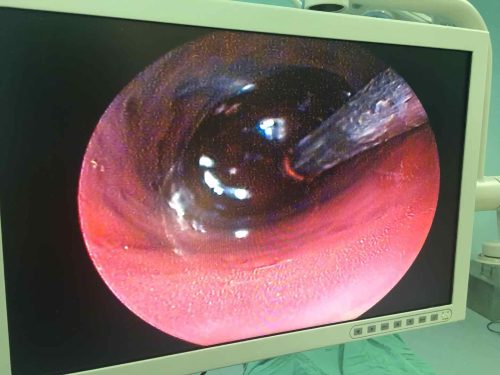

患者蔺某,男,60岁,因“突发剧烈头疼伴恶心呕吐2小时” 入院,经头颅CT检查证实为右侧小脑出血,血肿量约20毫升,血肿达脑干边缘并破入脑室系统。患者既往有高血压病史,入院时血压190/110㎜Hg。结合患者病史、症状、体征及头颅CT检查诊断为高血压性小脑出血。患者入院后病情急剧恶化,意识从清楚迅速转为浅昏迷,必须急诊手术清除小脑血肿。因出血位于小脑,该部位解剖结构复杂,又血肿临近脑干生命中枢,传统开颅手术存在切口大、创伤大、手术时间长等缺点,不利于术后神经功能恢复。而内镜手术损伤小、恢复快,翟德忠主任医师决定为患者施行内镜下小脑血肿清除术。手术在颅骨上仅仅开2厘米左右的骨孔,在内镜辅助下一次清除血肿,手术顺利,手术历时90分钟(比传统手术减少一半)。术后第二天患者意识清楚,四肢活动良好,复查头颅CT血肿清除满意(附图))。